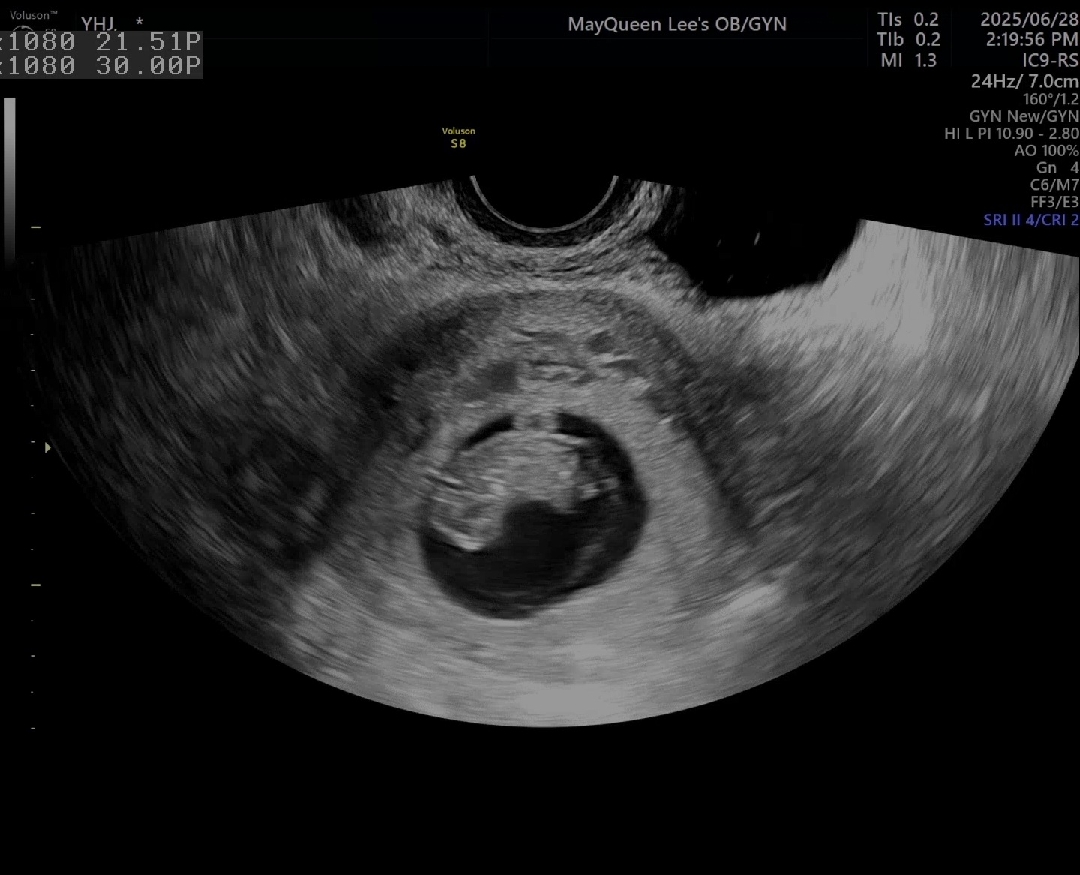

9주..젤리곰..?강낭콩..?

8주에 봤을때는 젤리곰같은걸 보여줬는데.. 남들 다 보신다는 9주에 강낭콩을 봤어요 ㅇㅁㅇ.. 딱풀아..엄마도 젤리곰 보여죠 ㅠㅠ